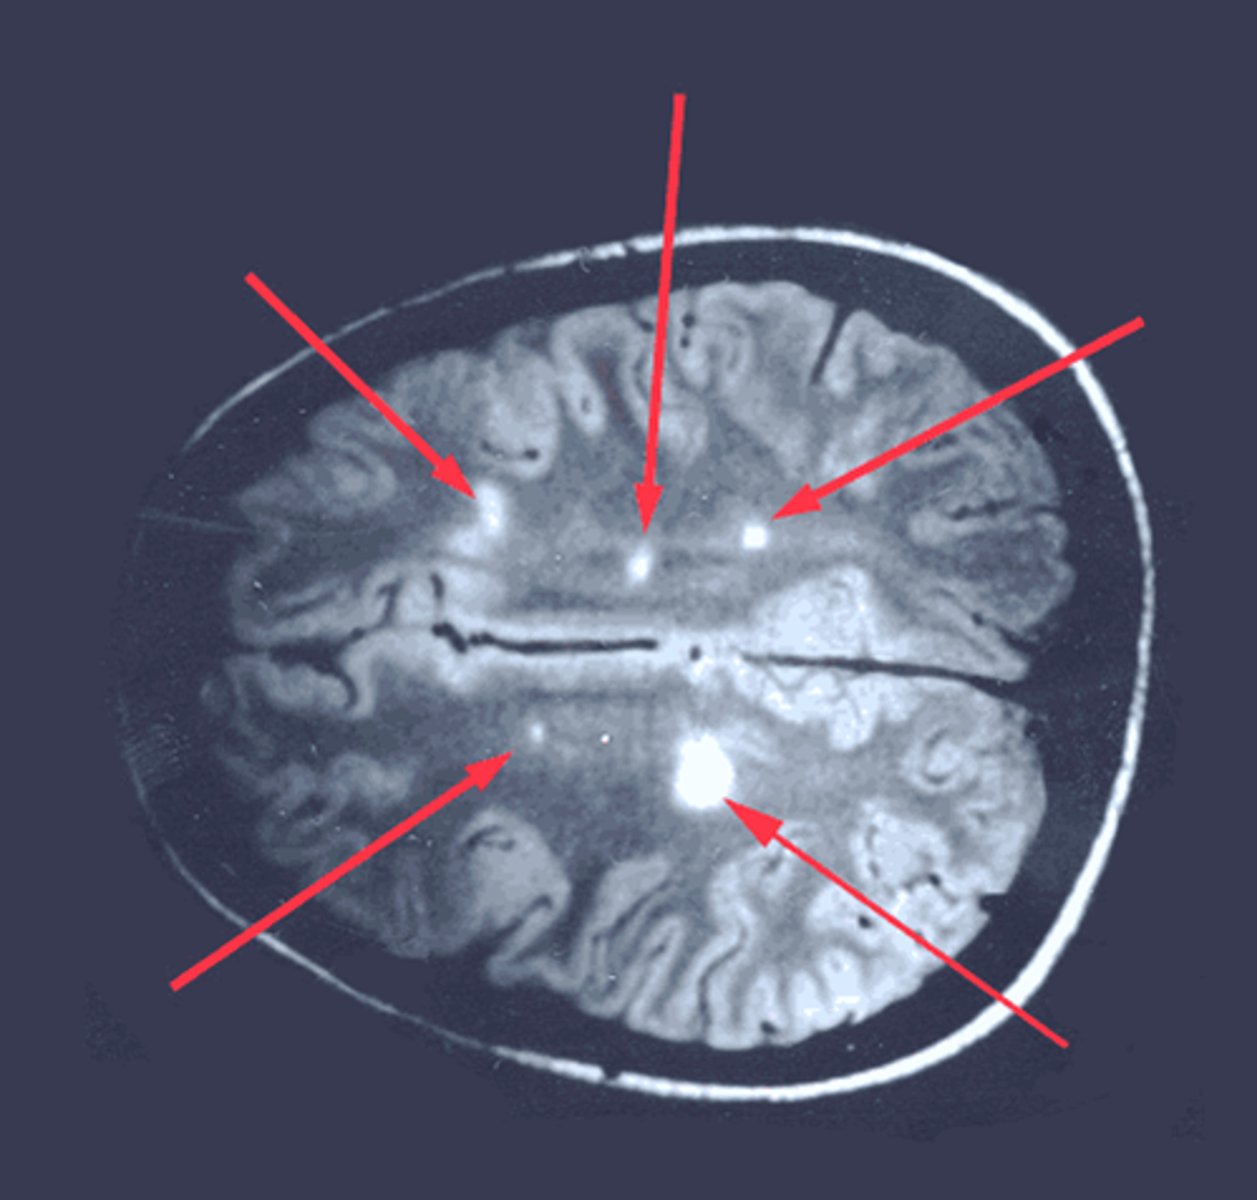

Nystagmus, intention tremor, scanning speech, bilateral internucular ophthalmoplegia

Muscular Sclerosis

Dx: Oligoclonal IgG bands and periventricular plaques on MRI